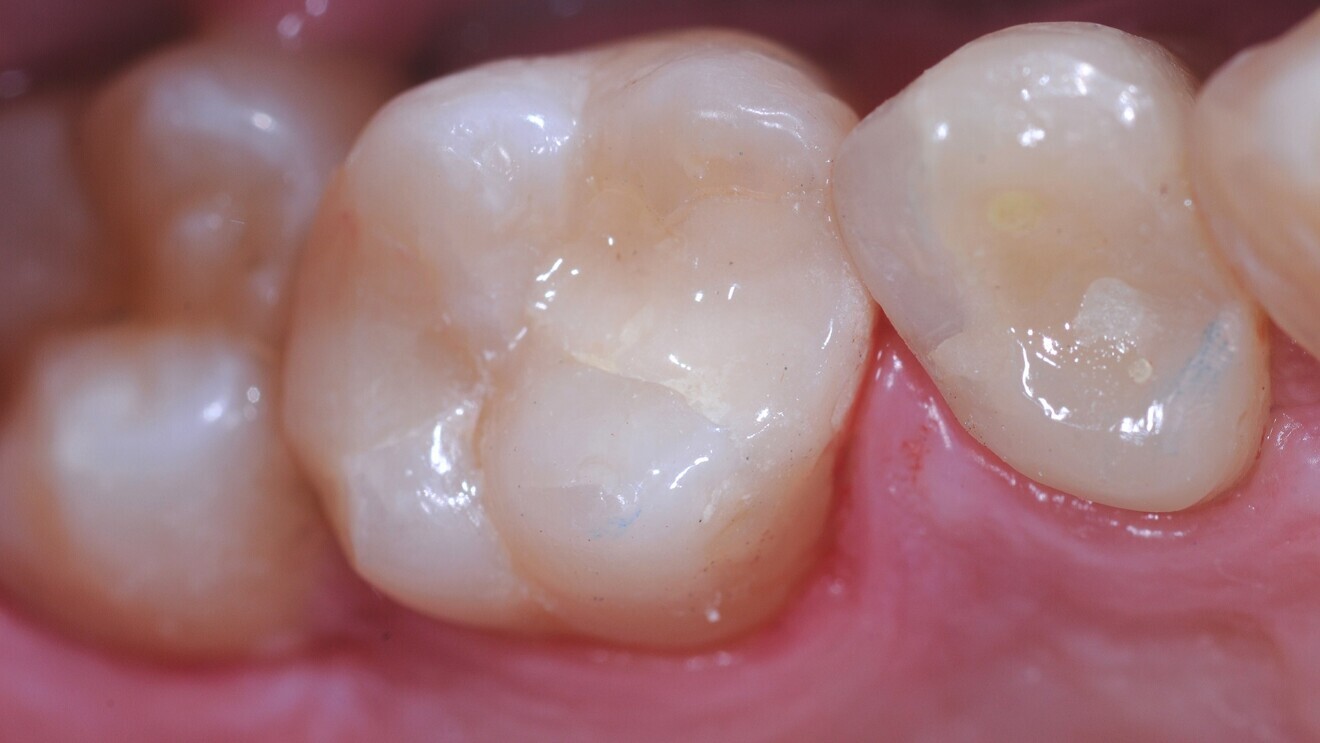

Cervical lesions (Figs. 1–3)

The cervical placement of glass ionomers, especially resin-modified glass ionomers, has a long tradition and is backed by a wealth of clinical studies demonstrating the usefulness of this material for this purpose. Resin-modified glass ionomers have consistently outperformed alternative materials when it comes to survival and success of cervical restorations.5 For glass hybrids, two randomised trials comparing this material against resin composites were identified.

The first study included a small sample of 25 patients with non-carious cervical lesions and bruxism.6 In these overall rather young patients, 148 lesions were randomly restored, indicating a massive clustering of the lesions per patient, with either a glass hybrid (EQUIA Forte, GC) or a resin composite (ceram.x one universal, Dentsply Sirona). After six, 12 and 24 months of follow-up, the restorations were re-evaluated using the modified United States Public Health Service (USPHS) criteria. When assessing the 126 remaining restorations in 22 patients at the 24-month recall, it was apparent that both materials had performed similarly. Only for marginal adaptation was a significant difference found, the glass hybrid showing slightly reduced adaptation. Secondary caries was not observed on any of the restorations.

Fig. 2: Cervical lesions restored with the glass hybrid EQUIA Forte.

Another study, with a follow-up of 36 months, assessed the survival, quality and costs of glass hybrid (EQUIA Forte) and resin composite restorations (Filtek Supreme XTE, 3M) for managing sclerotic non-carious cervical lesions.7 In 88 patients (50–70 years of age) with 175 lesions, restorations were placed directly without any mechanical preparation, which eventually resulted in high annual failure rates for both groups. Restoration quality was assessed at one, 18 and 36 months using the FDI World Dental Federation criteria. Costs were evaluated using a micro-costing approach (accounting for the time for material placement) and, during follow-up, fee items of the statutory insurance in Germany. Of the 88 patients, 43 received the glass hybrid (83 restorations) and 45 received the resin composite (92 restorations); cluster randomisation had been applied. At 36 months, 17 glass hybrid restorations and 19 resin composite restorations showed total retention loss, and five glass hybrid restorations had been partially lost. There was no significant difference between the materials. The FDI ratings were not significantly different for any domain except surface lustre. Here, the composite restorations were superior to the glass hybrid ones, although it should be noted that the latest generation of glass hybrids address such aesthetic effects. Costs were significantly lower for the glass hybrid restorations—both initially (€32.57; SD: €16.36) and in the long term (€41.72; SD: €25.08)—compared with the resin composite restorations (€51.60; SD: €26.17).

In summary, both studies—randomised trials of a robust design—indicate the suitability of glass hybrids for restoring cervical lesions. Moreover, they not only demonstrate that the material shows similar survival, but also flag the advantageous cost-effectiveness of this material. That glass ionomer materials work well for this indication is not necessarily new. However, aspects concerning the economic differences between composites and glass hybrids for managing cervical lesions had not been assessed in detail before. Regardless of the restorative material used, preparation of sclerotic surfaces is likely beneficial.